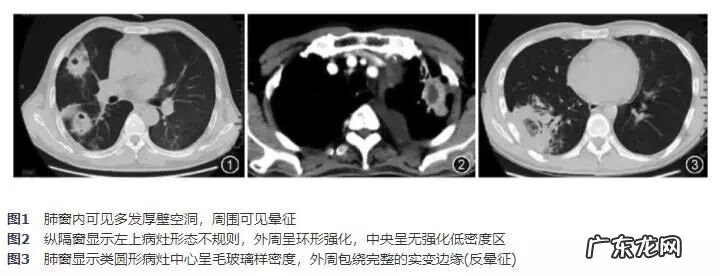

影像学表现:

所有病变均沿血管气管束分布,病灶最常累及右肺下叶(56%),其中贴近胸膜及叶间胸膜病灶16例(65%) 。形态以双侧多发实变(72%),结节团块影(68%)常见,胸腔积液8例(32%),多发厚壁空洞16例(64%)(图1),单发空洞3例(12%),内壁基本光滑,腔内含不规则密度影,其中有3例(12%)可见壁结节 。13例(52%)行增强CT扫描,实变及团块影内可见增粗的细小血管,8例(32%)空洞病灶呈不规则环形强化(图2) 。其他征象包括:新月征3例(12%),反晕征5例(20%)(图3),支气管累及5例(20%) (支气管中断1例、狭窄4例),单侧肺动脉栓塞2例(8%) 。2例因原发病出现肺门及纵隔淋巴结肿大 。